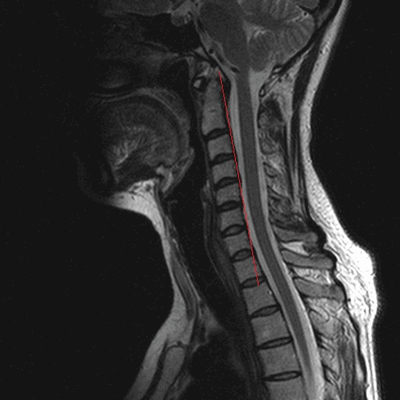

МРТ шеи: оценка спинного мозга (сагиттальная плоскость, Т2 последовательность)

МРТ шейного отдела позвоночника: оценка лордоза, сагиттальная плоскость, Т2 последовательность

Магнитно-резонансное сканирование: шейный отдел позвоночника в сагиттальной плоскости на Т1 ВИ